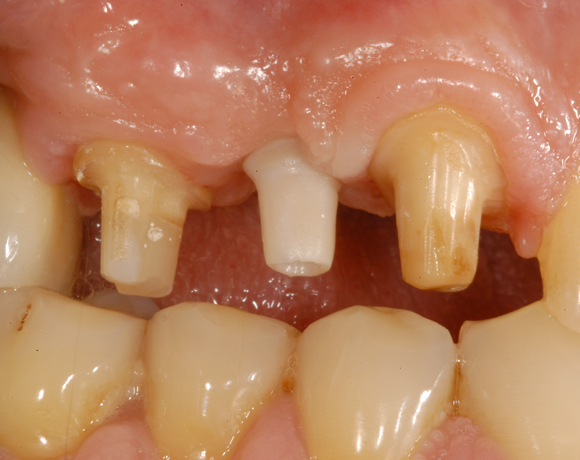

Der vorliegende Patientenfall war noch mit einem Prototypen eines vollkeramischen Aufbaus versorgt worden. Deutlich sichtbar der dunkle Rand an der VMK – Krone der metallkeramischen Versorgung. Die dunkle Verfärbung der Gingiva ist durch ein Amalgamtätoo bedingt.

Bei diesem Patienten wurden die Nachbarzähne und das Implantat vollkeramisch versorgt.